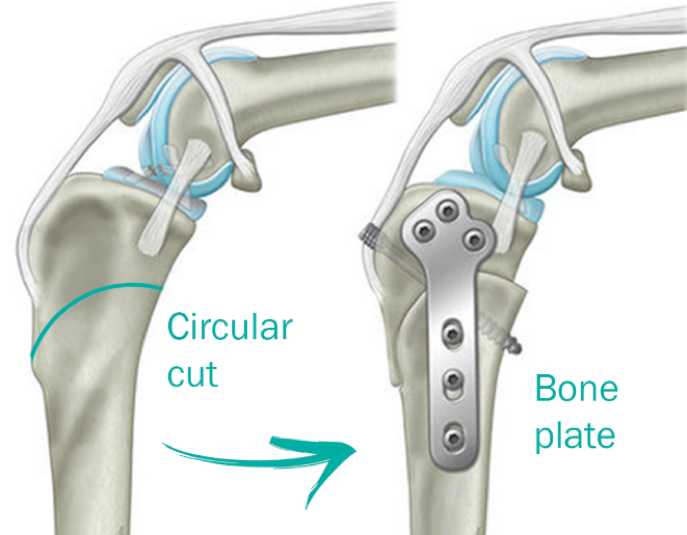

CORA-Based Leveling Osteotomy (CBLO)

CORA-Based Leveling Osteotomy (CBLO) is a specialized surgical procedure designed to treat ACL injuries in dogs with precision and effectiveness by combining the best aspects of the TPLO and TTA techniques. CORA stands for Center of Rotation of Angulation, a key principle in orthopedic surgery and joint geometry. By pinpointing the CORA, the surgeon can adjust the tibial plateau angle while aligning both the mechanical and anatomic axes of the tibia (this does not occur with any other method). In simpler terms, the CBLO procedure modifies the biomechanics of your dog’s knee to compensate for the damaged ACL. It does this not only by altering the angle of the tibial plateau, but also by pulling the patellar tendon and collateral ligaments slightly forward, enhancing stability and alleviating pain.

- Versatility for All Sizes and Ages: CBLO is suitable for dogs of all sizes and breeds, from small companions to large working dogs. One advantage of CBLO is that the osteotomy (cut through the bone) does not extend into the joint, as it does in a TPLO. For this reason, the CBLO technique can even be used in young animals that are still growing, as it does not jeopardize the growth plates.

- Enhanced Stability: CBLO changes the angle of the tibial plateau to reduce the forces exerted on the damaged ACL. By stabilizing the knee joint, it allows your dog to regain full mobility without relying on the torn ligament. This is the same principle used in the TPLO procedure. As an added bonus, CBLO nearly eliminates the “pivot shift” often observed in patients post-TPLO surgery and places less stress on the Posterior Cruciate Ligament (the counterpart to the ACL, which pulls in the opposite direction and is important in preserving joint health and stability).

- Faster Recovery Time: Many dogs undergoing CBLO show quicker recovery times compared to other procedures, including TPLO. This is due to a much larger surface area of cancellous bone-to-bone contact when the surgery is completed. CBLO creates a more stable construct at the osteotomy site, which improves early function and promotes faster healing.

- An Improved Osteotomy: Both TPLO and CBLO elegantly employ a crescentic saw blade to create a curved osteotomy with which bone fragments can be rotated into position. The CBLO uses a dome-shaped or convex crescentic osteotomy through the shaft of the tibia and does not affect the joint nor damage growth plates in young animals. Conversely, the TPLO involves creating a scoop-shaped crescentic osteotomy which starts inside the knee joint and exits through the back of the tibia. This increases the risk of bacterial contamination through the osteotomy (you can never truly close the joint), and carries a risk of leaving a thin stalk of bone at the front of the tibia which can – on rare occasions – fracture despite taking precautions.